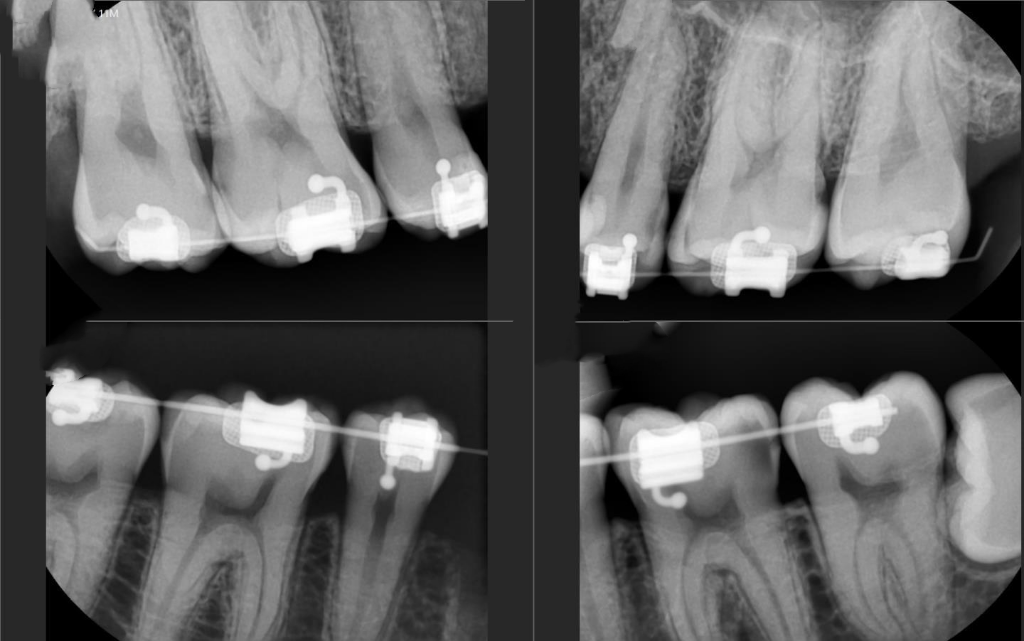

• 1번 째 사진

치아 사이가 전체적으로 많이 썩어 잇네요. 왼쪽 아래 뒤에서 두번쨰 #36번 치아는 충치가 많이 진행된거 같습니다. 신경치료 가능성이 높아보이긴 하네요.

들으신대로 다른 치아는 크게 문제는 아니지만 36번 치아의 경우에는 신경치료 가능성이 높습니다.